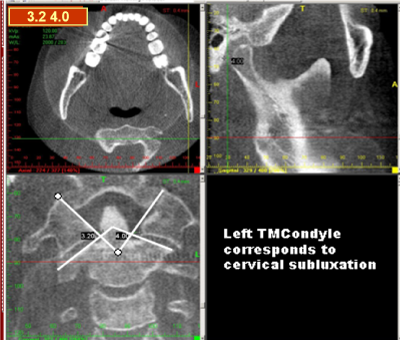

Figure 6. Reflex postural figures due to TOP BLOCK mechanisms

Figure 11. Left TMCondyle correspondence to cervical subluxation